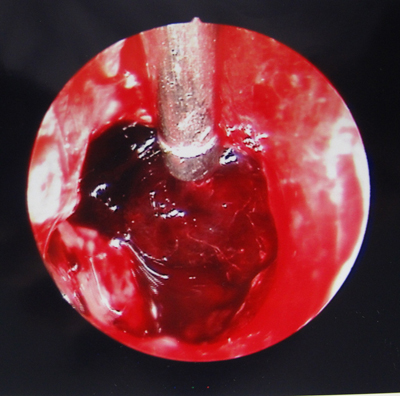

2011年6月23日,我院神经外科吕健副主任医师、宋千主治医师、权瑜医师共同为一例高血压脑出血患者成功实施我院首例全内镜下脑内血肿清除术。

患者男性,56岁,因“突发左侧肢体活动不灵19小时,意识不清18小时” 于2011年6月23日急诊收住我科,复查颅脑CT显示“右侧基底节区及丘脑出血(量约68毫升)并破入脑室”。完善各项术前准备后,在手术麻醉科张珍妮主治医师、薛鹏军以及我科宋琴的协助下,吕健副主任医师主刀、宋千、权瑜担任助手,在全麻下为患者施行了完全神经内镜下右侧基底节区血肿清除术,手术顺利,未输血,术后患者清醒,正在康复中。

近年来,随着微创神经外科的发展,神经内镜技术也已用于高血压脑出血的外科治疗。高血压性脑出血目前常用的手术方式包括锥颅血肿引流术和开颅显微镜下血肿清除术,前者创伤小,但是盲穿,后者能在直视下清除血肿,但创伤较大。全内镜下血肿清除术则兼具二者的优点,不仅能在直视下清除血肿,而且创伤更小,术中只需在皮层形成一个直径1 cm大小的操作通道即可,能够最大限度地保护正常脑组织。